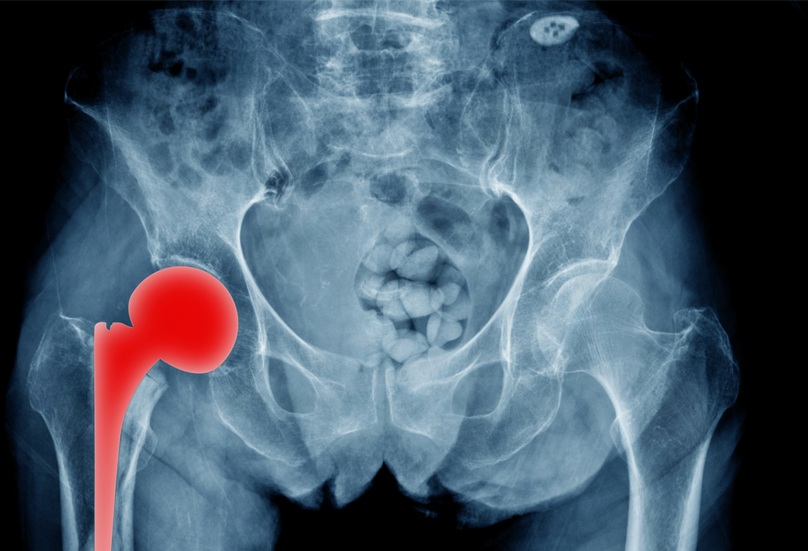

SuperPATH: Αποτελεσματική τεχνική για ολική αρθροπλαστική ισχίου

Η ολική αρθροπλαστική ισχίου είναι μια επέμβαση που κατά κύριο λόγο εφαρμόζεται ως τελική θεραπευτική λύση για την αντιμετώπιση της οστεοαρθρίτιδας του ισχίου

Ολική αρθροπλαστική ισχίου

Η ολική αρθροπλαστική του ισχίου βελτίωσε και συνεχίζει να βελτιώνει την ποιότητα ζωής εκατομμυρίων ασθενών εδώ και δεκαετίες. Ωστόσο, για μεγάλο χρονικό διάστημα παρέμενε μια βαριά, συχνά αιμορραγική επέμβαση που απαιτούσε μακρά νοσηλεία και αποκατάσταση. Στην πορεία των ετών η ορθοπαιδική χειρουργική εξελίχθηκε επιστημονικά και ταυτόχρονα εξελίχθηκε και η επιστήμη των υλικών που χρησιμοποιούνται στα χειρουργεία. Αποτέλεσμα αυτών των εξελίξεων αποτελούν οι νέες χειρουργικές τεχνικές που εντάσσονται στο χειρουργικό οπλοστάσιο του ορθοπαιδικού χειρουργού για την αντιμετώπιση της οστεοαρθρίτιδας του ισχίου.

Τεχνική SuperPATH

«Την τελευταία πενταετία στο MetropolitanHospital υιοθετήθηκε στην καθημερινή χειρουργική πράξη η τεχνική SuperPATH, μια σύγχρονη, εξελιγμένη τεχνική ολικής αρθροπλαστικής ισχίου με προσπέλαση ελάχιστης επεμβατικότητας, η οποία συνοδεύεται από επιστημονικά δεδομένα τεκμηρίωσης στη διεθνή βιβλιογραφία.

Στόχος της συγκεκριμένης χειρουργικής τεχνικής ελάχιστης επεμβατικότητας είναι η αντικατάσταση της άρθρωσης υπό συνθήκες μέγιστης προστασίας των μαλακών μορίων της περιοχής της άρθρωσης του ισχίου. Αυτό σημαίνει ότι πρώτιστο ζητούμενο αυτής της επέμβασης είναι το λειτουργικό αποτέλεσμα, ενώ το αισθητικό αποτέλεσμα που, μερικές φορές, προτάσσει ο ασθενής, παρανοώντας το συνολικό νόημα της επέμβασης, εξαρτάται από το μέγεθος της τομής που γίνεται για την προσπέλαση της περιοχής.